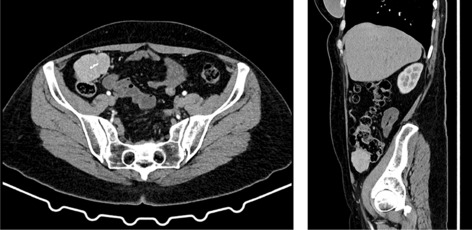

Result: The comparative analysis of the data shows a decrease in the number of presentations in ESU of AC cases during the pandemic, compared to the previous year, most often due to patients' fear of contacting the virus in the hospital environment. The median time between the onset of symptoms and the presentation in the ESU: 2020 – 14 days, 2019 – 5 days. Forms of moderate and severe AC predominated in the pandemic: GradeI—14.28%; GradeII—57.14%; GradeIII—28.57%. In 2019 GradeI—66.39%, GradeII—27.73%, GradeIII—5.88%. Laparoscopic cholecystectomy was attempted for all patients from the beginning, but the complications identified during surgery and severe forms led to a conversion rate in 2020 of 14.28%, compared to 5.88% in 2019. The severity of the cases is also observed in the postoperative complications encountered (perihepatic abscess Fig. 2. Figure 2, wound infection, bile leak; 2019—5.04%, 2020—23.21%), which required surgical reinterventions to solve them (2019: 2.52%, 2020: 10.71%). The number of deaths was significantly higher in 2020 (5.35%), compared to 2019 (0.84%).